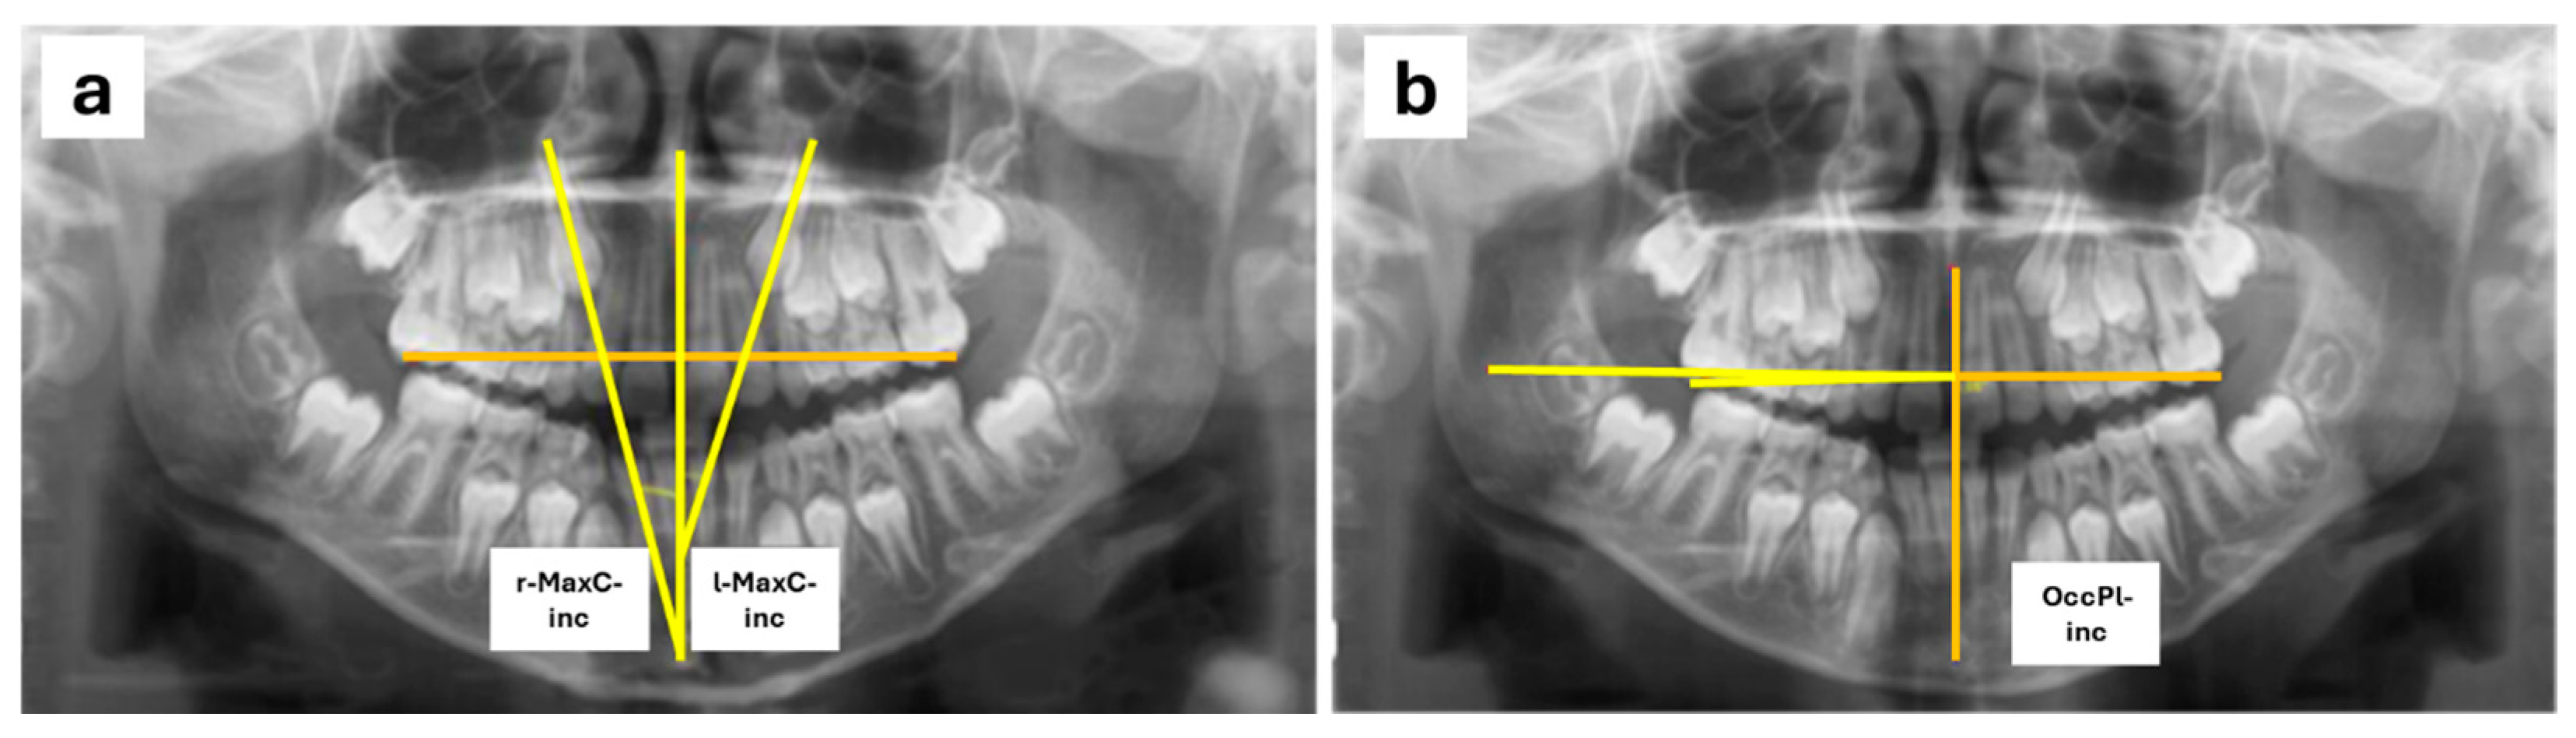

For the measurements, a reference plane was set up using the midline passing through the midpoint of the palatal suture and the anterior nasal spine. To assess MaxC-inc, the angle between the reference plane and a line following the longitudinal axis of the maxillary canines was measured (Figure 1a) following the Power–Short and Canut techniques [30,31]. For the measurement of OccPl-inc, the occlusal plane was defined by drawing a line passing through a point at the center of the occlusal surface of the permanent first maxillary molars or, if the permanent molars had not yet erupted, the second maxillary primary molars. A line perpendicular to the reference plane was drawn at the point where it intersected the occlusal plane on the right side of the patient, and the angle formed between this perpendicular to the midline and the occlusal plane was measured (Figure 1b). Also, right (r-) and left (l-) sides were evaluated.

Figure 1. Radiographic measurements conducted in orthopantomographies: MaxC-inc (a) and OcclPl-inc (b).